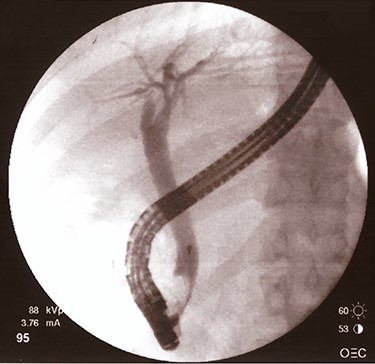

After fourth month, laboratory tests were normal so ERCP with removal of plastic biliary stent was performed and cholangiography post-removal showed a free and restored biliary tree (Fig. 4).